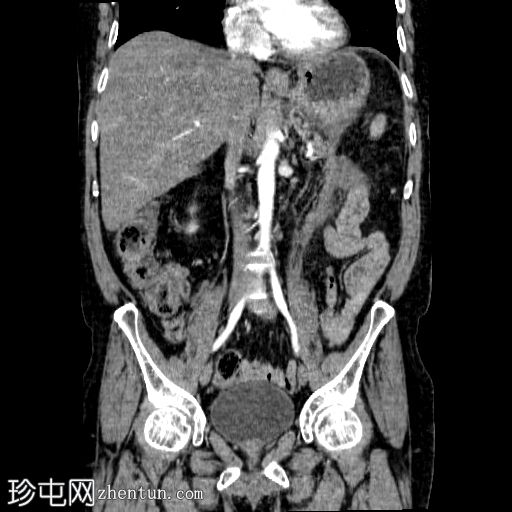

2.jpg

冠状面

非造影

胰体尾弥漫性增大,特征为胰腺实质低强化,无明显坏死区域。

该病灶与以下表现相关:

胰周筋膜平面边界不清的污迹,无明显壁形成、气室、固体碎片或血液产物。

多个亚厘米大小、非特异性的腹主动脉旁淋巴结和肠系膜淋巴结,可能具有反应性。

病变范围如下:

病变横向延伸至左前肾旁间隙,伴有Gerota筋膜增厚。

病变向下延伸至盆腔。

无肠系膜或脾脏血管阻塞的证据。

未见导管扩张或钙化。